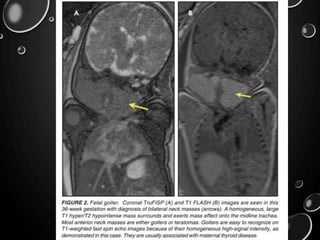

• EVALUATION OF FETAL GOITERS, ALTHOUGH RARE, CAN

ALSO BE DONE THROUGH T1 FLASH SEQUENCES

• TRUFISP IS A WHITE-BLOOD SEQUENCE THAT PROVIDES AN

ALTERNATIVE WAY OF LOOKING AT FETAL ANATOMY.

• FLASH - EVALUATION OF FETAL STRUCTURES WITH

NORMALLY HIGH T1 SIGNAL, INCLUDING THE THYROID,

LIVER, AND MECONIUM.